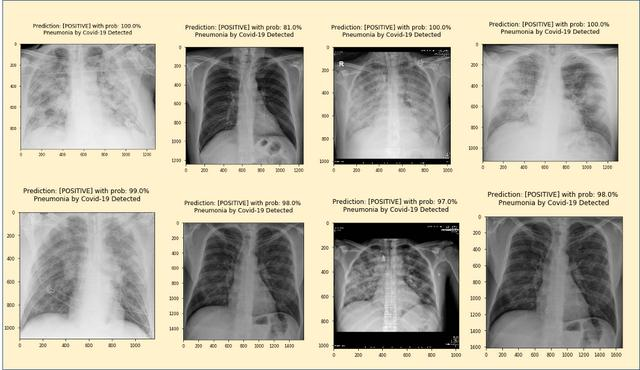

通过更改其余7个图像的imagePath值,我们获得以下结果:

所有图像均呈阳性,确认100%灵敏度。